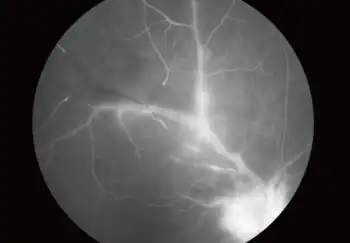

| Angiogram of papillitis and vasculitis in an ocular toxoplasmosis individual | |